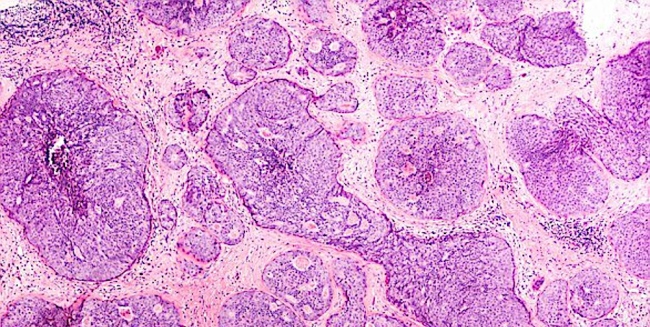

IMEJ menunjukkan sel barah payudara yang dirakam dan diperbesarkan menggunakan mikroskop.